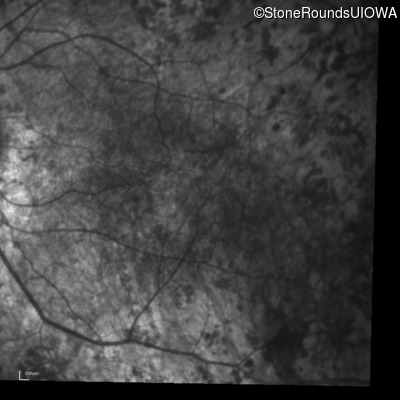

Infrared Fundus Photograph - Right - 20/250 sc

Exemplar